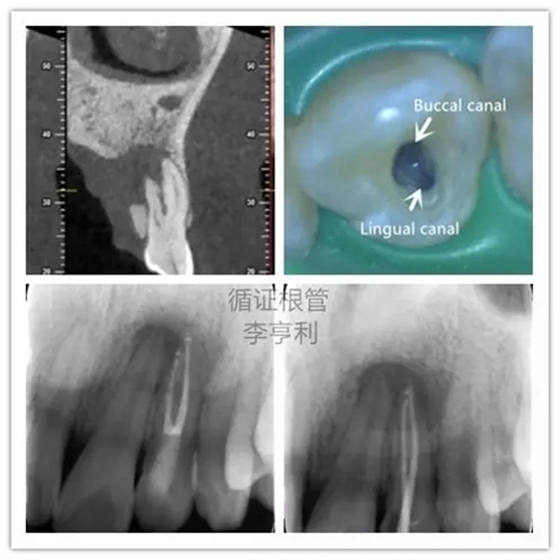

5,根管解剖的評(píng)估

上頜側(cè)切牙擁有雙根管

在CBCT的掃描中,根管形態(tài)能在三維的條件下評(píng)估,能準(zhǔn)確顯示根管數(shù)量和多個(gè)根管之間的聯(lián)系。根據(jù)Matherne et al. (2008)的間接體外研究(ex vivo),牙體牙髓專科醫(yī)生單憑閱讀數(shù)碼X片,即使一個(gè)牙齒進(jìn)行多個(gè)角度拍攝,還是有40%的樣本牙齒出現(xiàn)至少一個(gè)遺漏根管。

對(duì)于最容易被疏忽的上頜磨牙MB2根管,CBCT正確判斷其是否存在的幾率高達(dá)79%,與金標(biāo)準(zhǔn)的牙齒切片(sectioning)準(zhǔn)確率無(wú)統(tǒng)計(jì)學(xué)上的區(qū)別(Blattner et al. 2010)。所以,即使對(duì)于非手術(shù)性的根管再治療(non-surgical retreatment),CBCT也能提供巨大的治療價(jià)值。